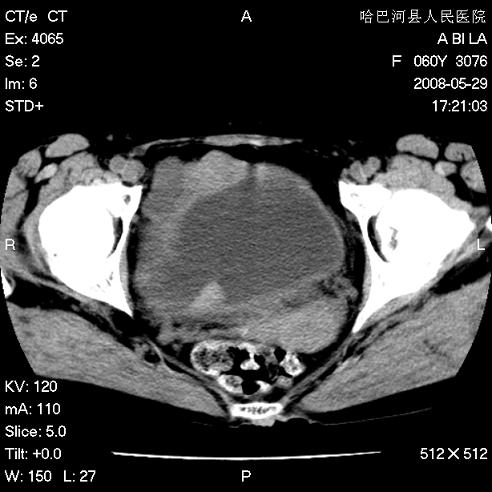

标题: CT13730:排尿不畅4天,抗炎治疗无效,现尿中可见血块 [打印本页]

标题: CT13730:排尿不畅4天,抗炎治疗无效,现尿中可见血块

膀胱内多发恶性占位,癌可能性大

手术结果及病理:膀胱癌并膀胱壁转移,膀胱内血块